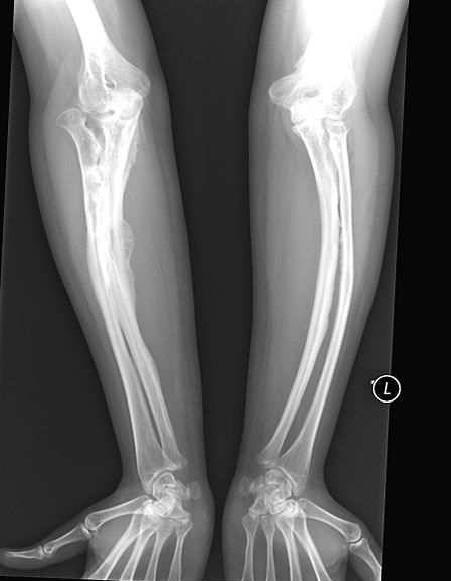

Žena se zvýšenou křehkostí kostí dokázala šťastně vyjít oženit se. Anastasia Marukova, která byla diagnostikována jako dítě „nedokonalá osteogeneze,“ přežila mnoho problémů. Ona je zlomil kosti 40krát. Otec nemohl vydržet život s vážně nemocným dcera a nechala je brzy se svou matkou. Ale Anastasia měla štěstí manžel – milovaný ji doprovodil všude, protože nedbalý hnutí jí slibuje nový zlom.